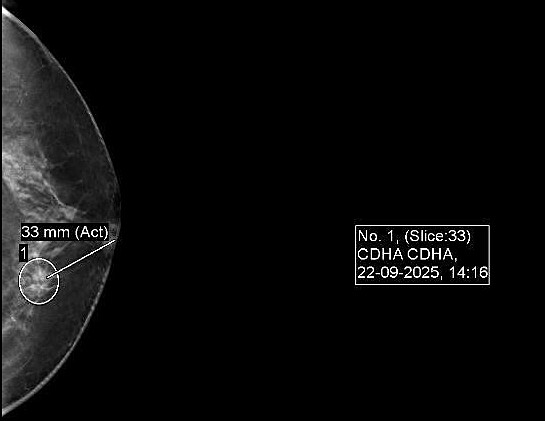

Image of a lesion with intermediate suspicion of malignancy. Photo: Tam Anh General Hospital

Ngan, a 51-year-old woman, discovered a suspicious lesion during a routine health check-up at Tam Anh General Hospital Hanoi. Mammography and breast computed tomography revealed a 5,9x5,4 mm lesion in her left breast, classified as BIRADS 4B, indicating an intermediate suspicion of malignancy.